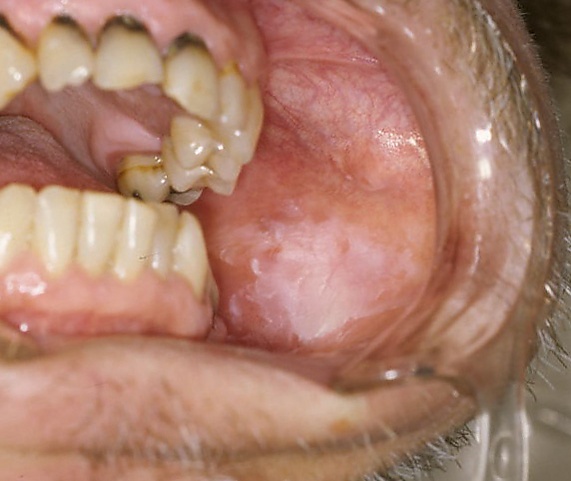

Лейкоплакия

Лейкоплакия (новолат. leucoplakia от др.-греч. λευκός — «белый» + πλάξ, родительный падеж πλακός — «пластинка»; синоним — лейкоплазия) — заболевание, характеризующееся поражением слизистых оболочек, ороговением покровного эпителия разной степени выраженности[1][2]. Поражаются только слизистые, выстланные многослойным плоским или переходным эпителием[3].

- Плоская лейкоплакия имеет вид резко отграниченного сплошного помутнения оболочки, иногда напоминающего плёнку, которая не снимается при поскабливании шпателем. В зависимости от интенсивности ороговения цвет поражения варьирует от бледно-серого до белого. Поверхность лейкоплакии сухая и слегка шероховатая. Очертания очага, как правило, зубчатые. Уплотнения в основании участков ороговения не бывает. По периферии очагов ороговения в углах рта иногда возникает небольшая гиперемия. На щеках очаги лейкоплакии могут иметь складчатый вид, на дне полости рта — вид морщинистой плёнки серовато-белого цвета.